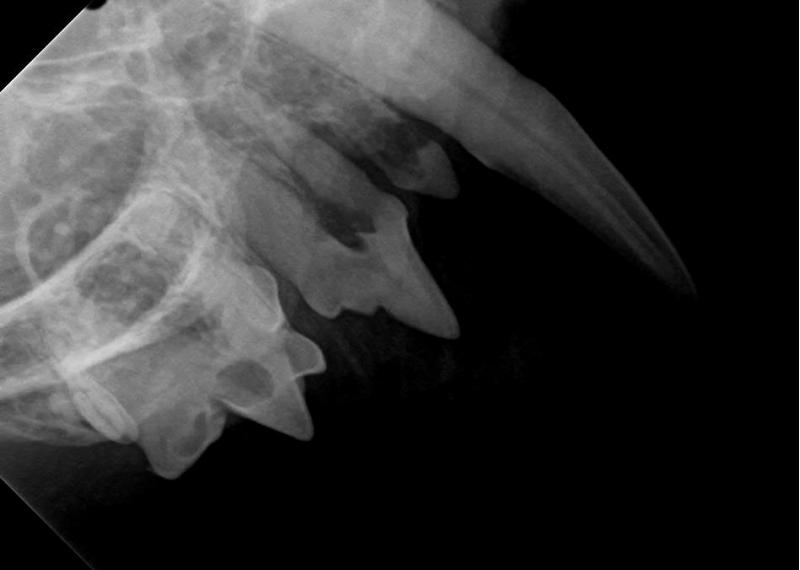

Uw dier zal onder sedatie gebracht worden (u mag hierbij aanwezig zijn) en wordt daarna geïntubeerd. Gedurende de behandeling zal uw dier steeds gemonitord worden. Wij beschikken over professionele apparatuur om het gebit van uw dier in onze kliniek te onderzoeken en te behandelen. Door middel van een pocketsonde en dentale röntgen kunnen we eventuele problemen makkelijk opsporen. Denk hierbij aan fracturen, wortelresten, botproblemen, glazuurdefecten, furcaties (ruimte tussen de kieswortels), gingivitis (tandvleesontsteking), stomatitiscomplex (mondvliesontsteking) of rotte tanden en wortels.